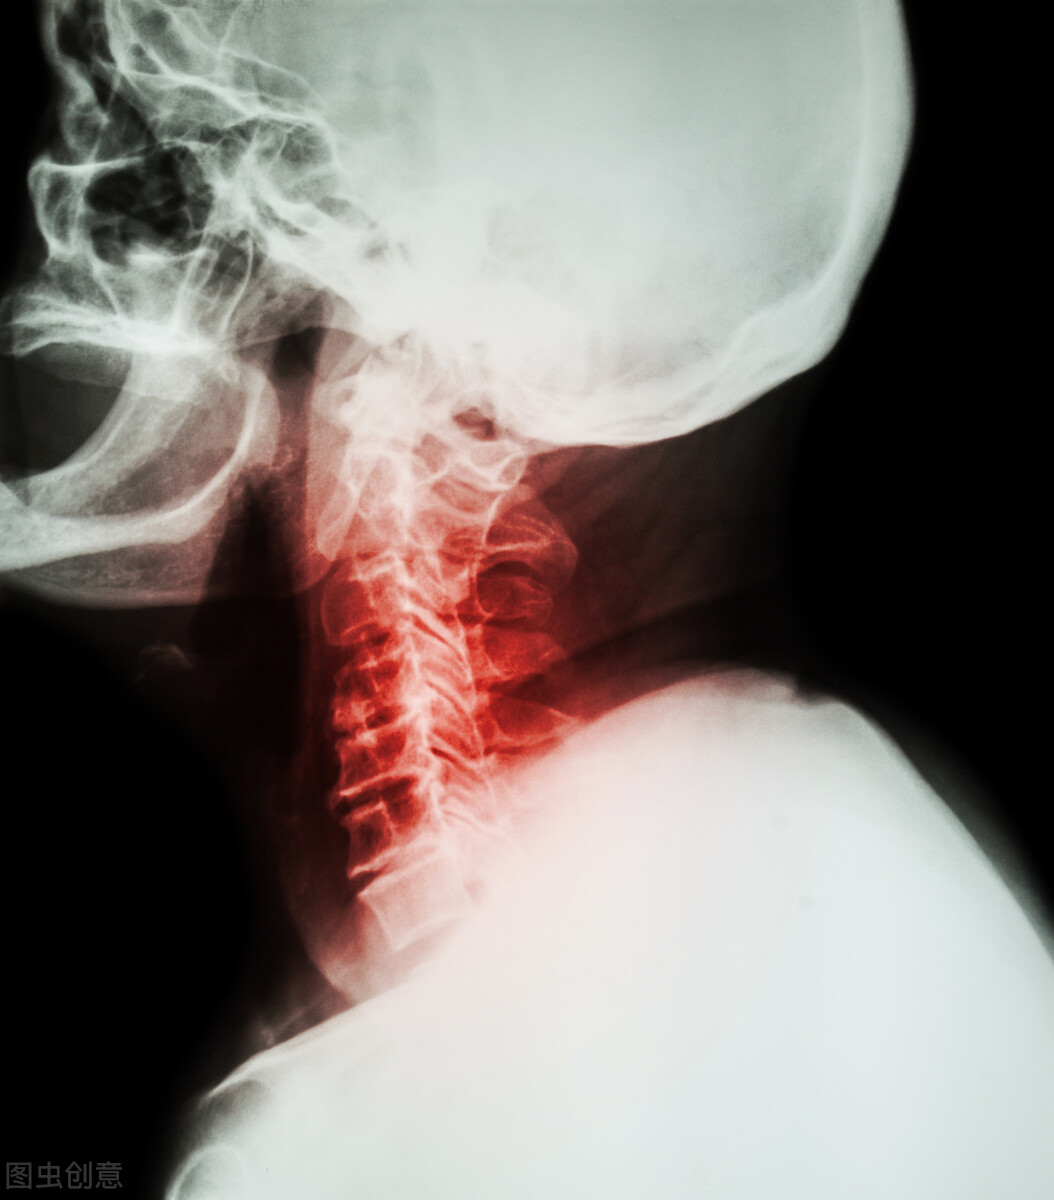

从核磁来看,患者的颈部存在多处病变,影响了 颅脑后循环血供 ,时间长了以后就容易导致脑细胞缺血、缺氧,且 这些 病灶会对周围的神经根进行压迫和刺激,会破坏神经系统的正常状态,使其发生紊乱,让相应的血管痉挛收缩 。

血管是血液得以流动的通道,更是心脏向大脑供血的必经之路,当 血管发生痉挛收缩时,会使得身体内部的血液流量大幅度减少 ,而且随着血管的痉挛收缩,血管局部平滑肌受损,发生出血,会加速血栓的形成,最终影响血液的正常流动,从而引发脑梗。

相应大家不难发现,我们的颈部有一个Y字型的分叉,那是我们的颈动脉,因为比较浅显,所以我们用手都可以摸到,当颈椎出现病变时,颈动脉是直接“受害人”,这种独特的外形更易发生颈动脉堵塞。

当颈动脉发生堵塞时,血液就无法有效的为大脑供血,这就必然导致大脑区域组织的缺血、缺氧甚至是坏死,也就导致了脑梗。